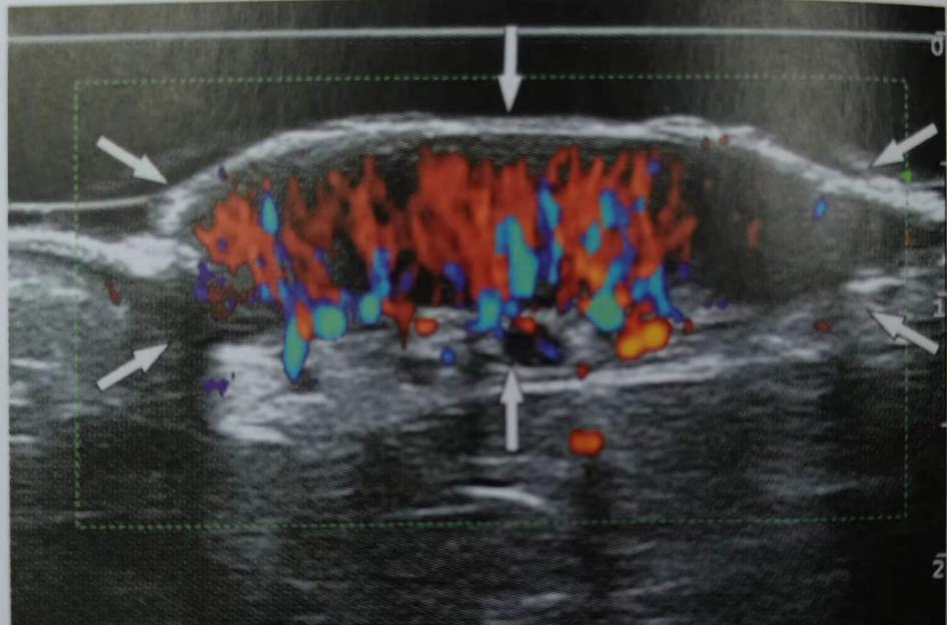

(5)評估炎性疾病對皮膚的累及程度及竇道形成、積液等情況。

如:皮膚水腫、脂膜炎、蜂窩織炎、銀屑病、痛風(fēng)等。

圖片

蜂窩織炎